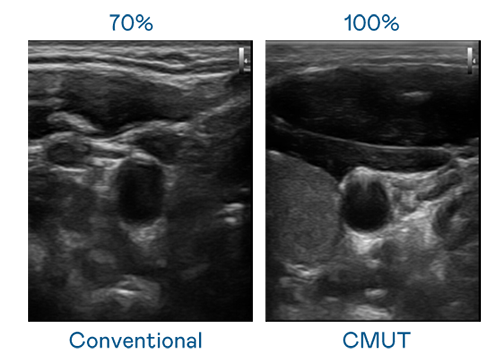

CMUT 技术是一种用电容式微机电元件来产生超音波讯号的技术。与传统 PZT 压电式技术相比,CMUT 频宽增加 30%,更宽频的超音波讯号让影像解析度大幅提升,是实现高影像品质医疗超音波扫描、促进精准医疗发展的关键技术。

超音波影像的解析度高低,首先取决于探头能发出的讯号频宽。金年会金字招牌信誉至上入口 CMUT 可提供高清晰的超音波讯号,提供高频宽、高灵敏度、影像纹理细节更高的超音波影像,协助医护人员缩短影像判读时间及利用精准的医疗影像进行诊断。